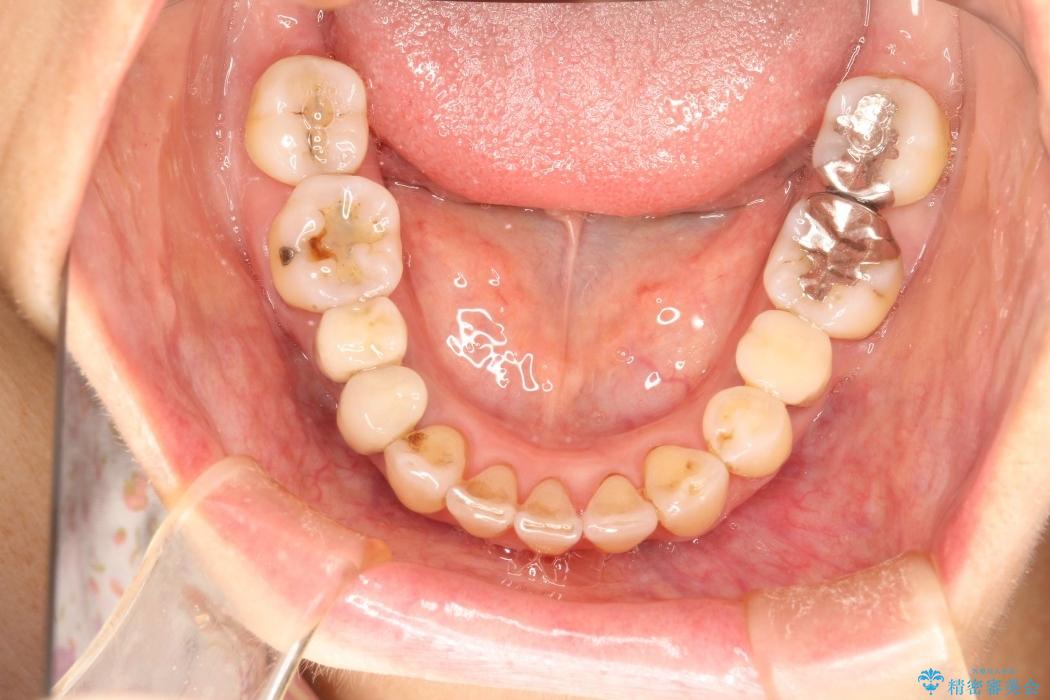

【50代女性】八重歯のインビザライン矯正 治療例

八重歯の改善を希望され来院されました。

当初はセラミックでの治療を希望されていましたが、噛み合わせと歯並びを治していく為に矯正治療を提案させていただき、インビザラインでの矯正を行う計画にしました。